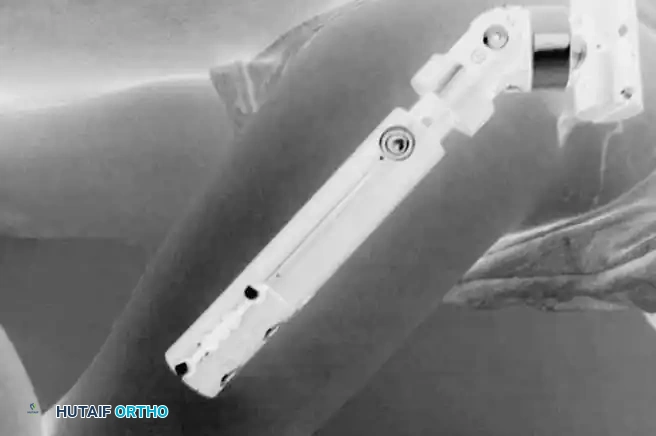

Surgical Management: Femoral Varus Derotational Osteotomy (VDRO)

Surgical containment is indicated for children over the age of 8 with Herring Group B or B/C disease, or any child exhibiting progressive loss of containment and "head-at-risk" signs.

The Femoral Varus Derotational Osteotomy (VDRO) is a powerful technique that redirects the vulnerable anterolateral portion of the femoral head deeply into the acetabulum, relieving it from the deforming forces of the acetabular rim.

Step-by-Step Surgical Technique:

1. Positioning: The patient is placed supine on a radiolucent Jackson table. A bump is placed under the ipsilateral hip.

2. Approach: A standard lateral approach to the proximal femur is utilized. The fascia lata is incised, and the vastus lateralis is elevated off the intermuscular septum and reflected anteriorly to expose the proximal femoral shaft.

3. Guidewire Placement: Under strict fluoroscopic guidance, a guidewire is advanced into the femoral neck and head, parallel to the planned angle of the blade plate. The goal is typically to achieve a neck-shaft angle of 110 to 115 degrees.

4. Osteotomy: A transverse or closing-wedge osteotomy is performed at the intertrochanteric level using an oscillating saw.

5. Derotation and Varus: The distal fragment is externally rotated (typically 15-20 degrees) to correct the anteversion, and the proximal fragment is allowed to fall into varus.

6. Fixation: A pediatric locking plate or a fixed-angle blade plate is impacted into the proximal fragment and secured to the distal shaft with cortical screws. Compression is applied across the osteotomy site.

Postoperatively, the varus angulation results in a temporary limb length discrepancy and a Trendelenburg gait, which typically resolves as the child grows and the neck-shaft angle remodels.